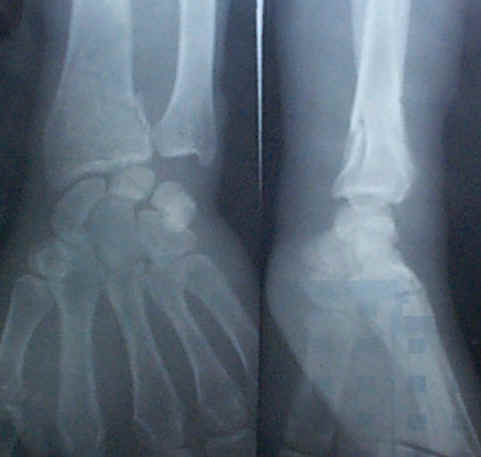

廖荣,男,汉族,出生于1991年4月13日,江西省万载县三兴乡红旗村14组。1999年5月30日在和别人玩时,不小心跌伤左手,经三兴卫生院摄片诊断左手尺骨、桡骨骨折、错位。如图。摄片后就来找我医治。我先用手法使其折骨复位,贴二个小号膏药包扎固定。该小孩第二天照常上学,晚上能安静睡。换一次膏药,20多天后患者康复如初。